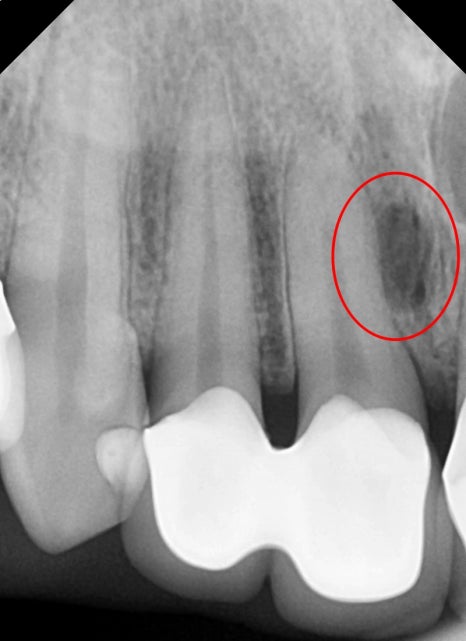

자세히 보기 위해 엑스레이를 찍어보았습니다.

뿌리끝 염증과 측면 쪽 염증 신경치료 후 앞니 보철치료 진행

엑스레이에 선명하게 보일 정도로

이미 안쪽으로 염증이 생긴지 수개월 된것으로 보여집니다.

이런 경우는 과거에 제작한 크라운을 제거하고

안쪽에 깨끗하게 신경치료 후 치아 외형에 맞게

심미보철물을 다시 제작을 해야 합니다.

이때, 2개 치아를 한 덩어리로 묶인 보철물은

어쩔 수 없이 같이 제거하고 하나씩 따로 제작을 합니다.